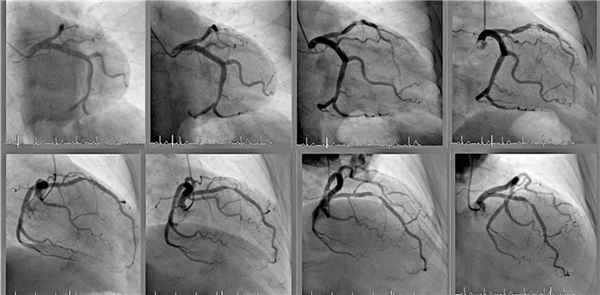

Ангиография коронарных сосудов или коронарография

Ангиография коронарных сосудов также называется коронарографией. При таком вмешательстве катетер вводится в бедренную артерию или в лучевую артерию на запястье. До аорты катетер продвигается под контролем рентгена. После того как трубка достигает нужных сосудов, подается контраст. Его введение осуществляется поочередно в правую и левую артерии. Рентгеновские снимки делают тогда, когда контраст заполняет просвет сосудов сердца.

При заполнении сосудов контрастным веществом пациенты отмечают временное ощущение жара (преимущественно в области лица). Также возможны нарушения сердечного ритма. Обычно они провоцируются прикосновениями катетера к стенкам сердца. В некоторых случаях из-за общего снижения артериального давления пациенты испытывают головокружение. Редкими побочными эффектами являются тошнота и кашель.

При ангиографии коронарных сосудов (коронарографии) используется доступ через бедренную или лучевую артерию. Для этого вида ангиографии предназначен более длинный проводник. Когда катетер достигает сосудов сердца и вводится контрастное вещество, осуществляют серию снимков. При необходимости, это может быть компьютерная томография. С помощью ангиографии можно проводить лечебные процедуры. Для этого по проводнику заводят баллонный катетер или стент.